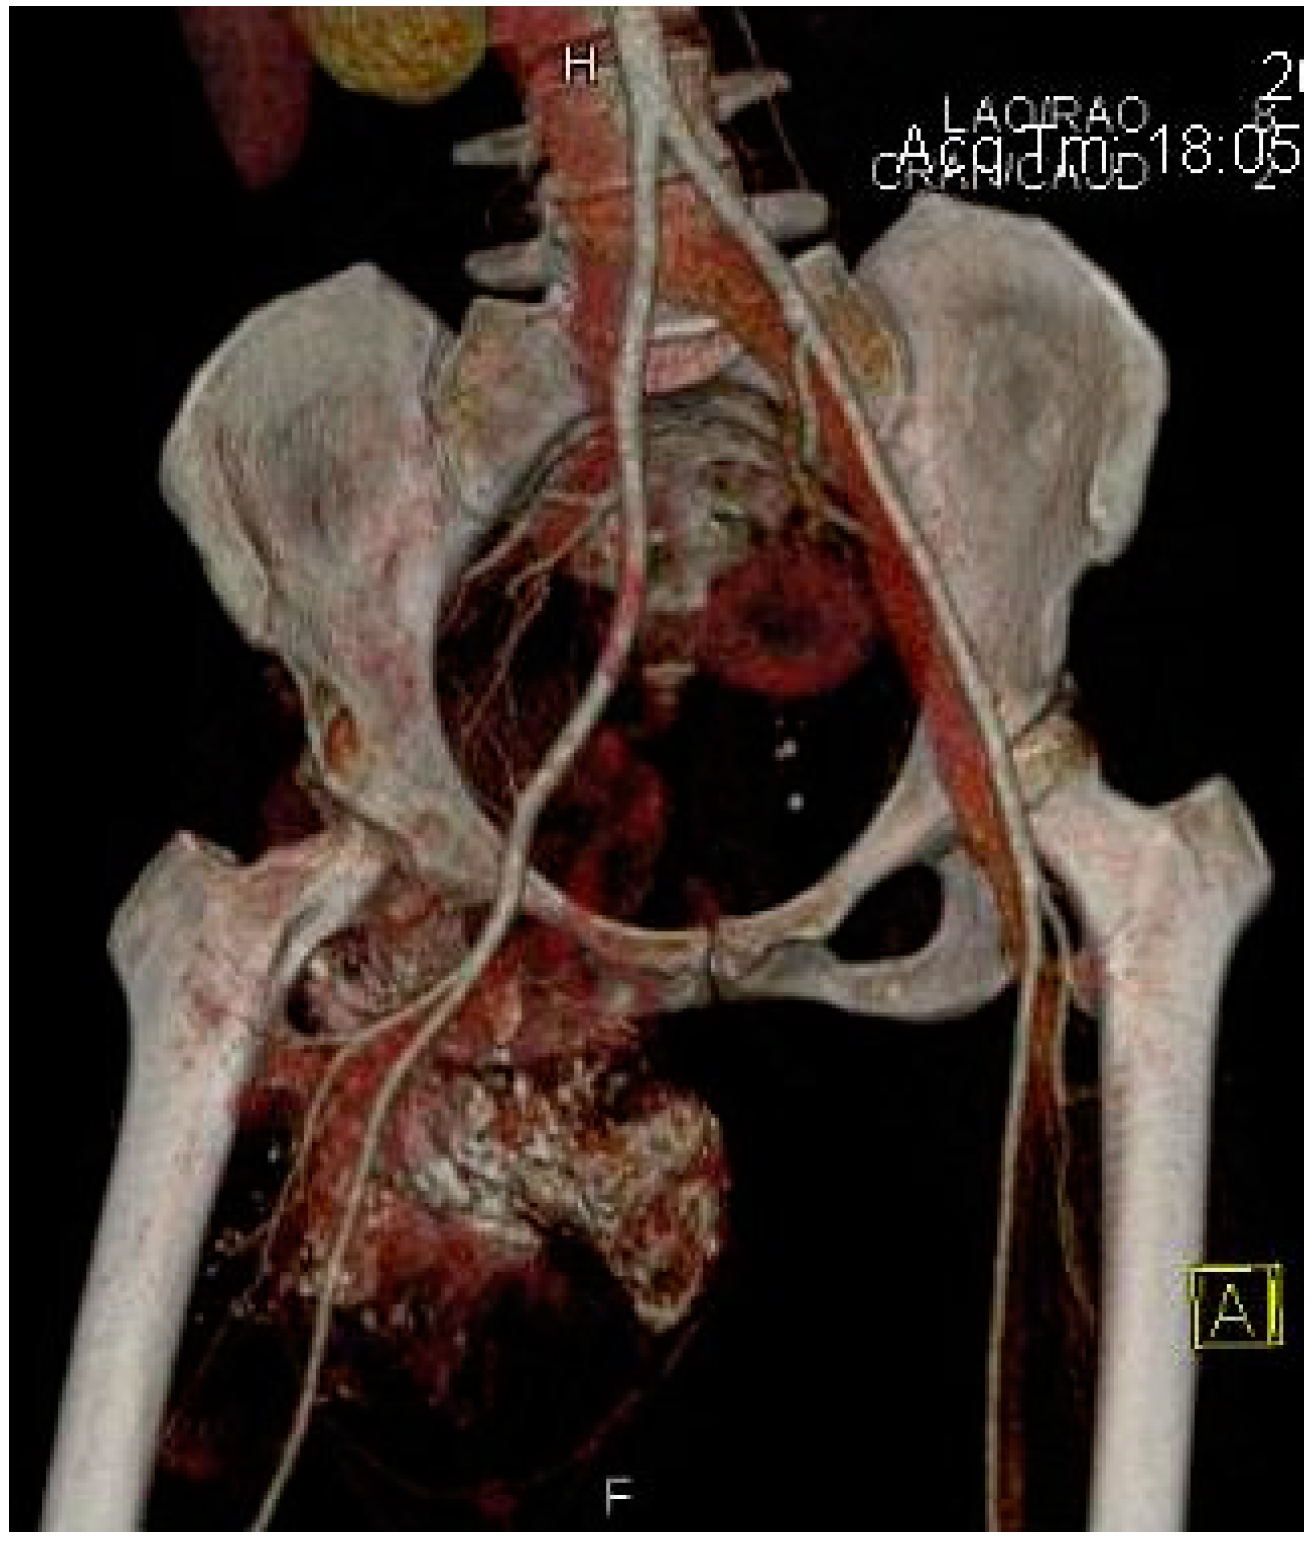

2.2. Imaging Examinations